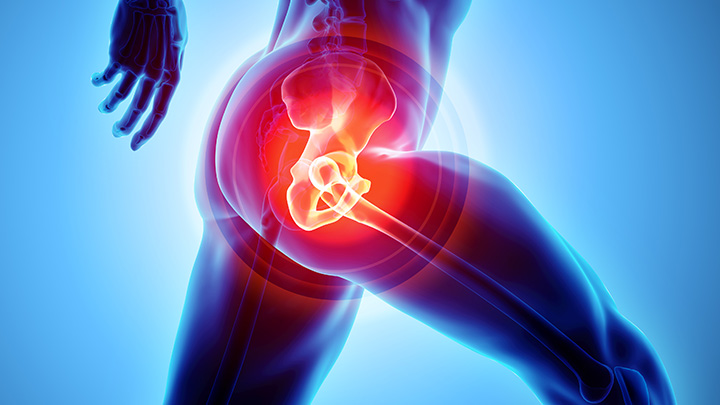

Lesões degenerativas avançadas

Ao longo dos anos, pode haver o desgaste das articulações dos quadris, podendo ser acompanhada ou não de quadros de dor local